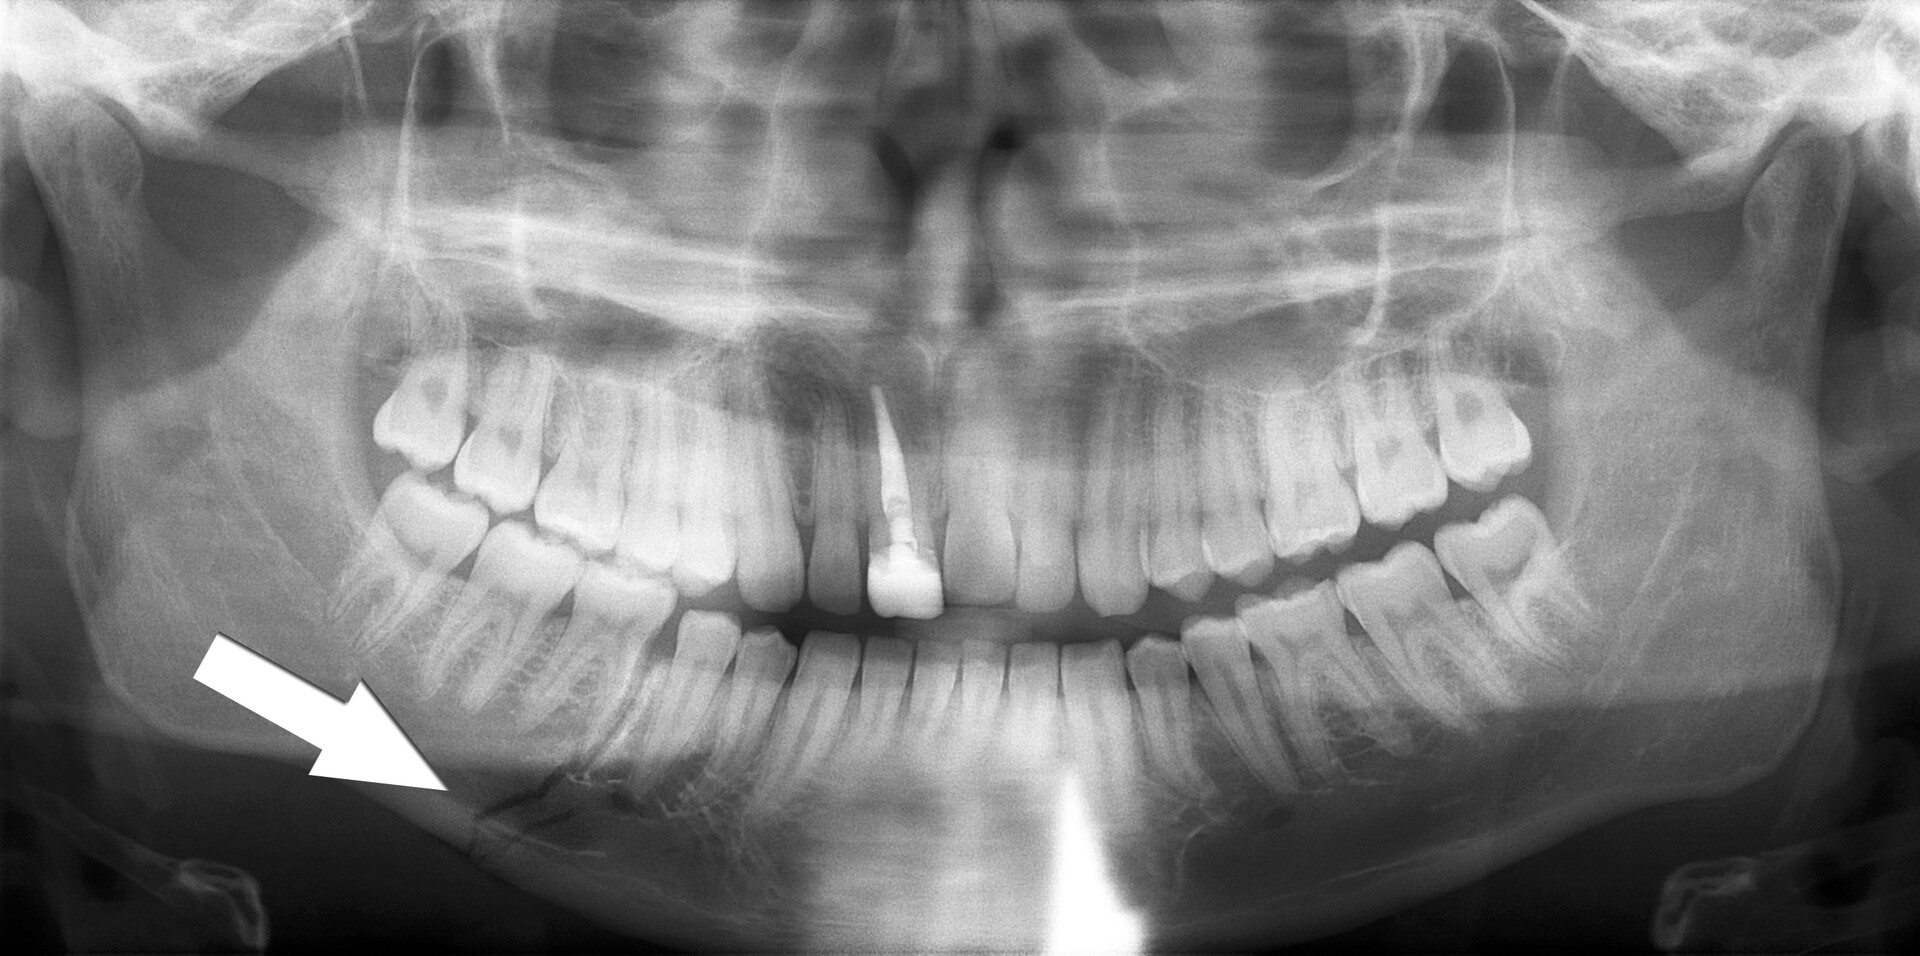

Рентгенография небного шва: Медицинские исследования и диагностика